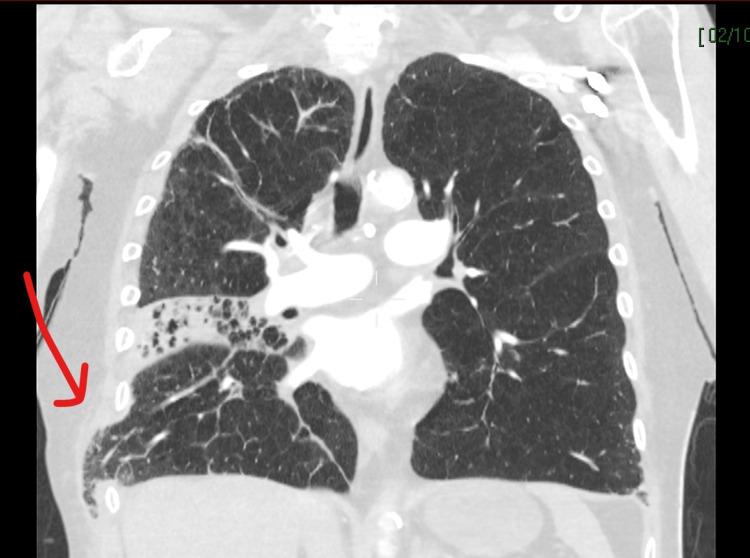

由于突然晕倒,患者接受了诊断性影像学检查:包括头部、胸部和腹部的CT,以排除肺栓塞和颅内出血导致的心脏骤停,以及确定败血症的来源。CT显示患者右下、中、上肺叶实变伴双基底不张,可能是败血症的病因。多重双侧前肋骨骨折,与心肺复苏术保持一致,右肺通过右胸壁突出(图1-2)。入院前一个月的高分辨率CT可用于比较,两份CT报告均显示持续广泛的肺气肿改变。

图1   胸部CT (冠状位) 显示第八肋下右侧肺疝和中叶实变。红色箭头指向肺疝